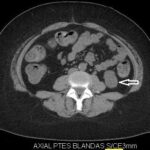

Fase sin contraste o basal

En la exploración renal se debe incluir esta frase dentro del protocolo; la fase proporciona la información inicial de una masa tumoral sospechosa, lo que permite tener un punto de referencia al compararse con las fases post-contraste. Los valores mayores a 12 UH son sospechosos de malignidad; teniendo en cuenta que el CCR es un tumor vascularizado, su atenuación aumenta a 20.

UH o más; si dichos tumores son mayores a 3 cm tienen características más heterogéneas en comparación con los tumores menores a 3 cm, que son más homogéneos.

Las calcificaciones se encuentran hasta en un 30% de los CCR y son más fácilmente visibles durante la fase basal 3-4 (Fig. 1).